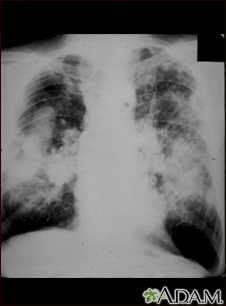

Coal workers pneumoconiosis, complicatedBackCoal workers pneumoconiosis, complicatedThis picture shows complicated coal workers pneumoconiosis. There are diffuse, massive light areas that run together in the upper and middle parts of both lungs. These are superimposed on a background of small and poorly distinguishable light areas that are diffuse and located in both lungs. Diseases which may explain these x-ray findings include, but are not limited to: complicated coal workers pneumoconiosis (CWP), silico-tuberculosis, and metastatic lung cancer. E-mail FormEmail ResultsName:Email address:Recipients Name:Recipients address:Message: